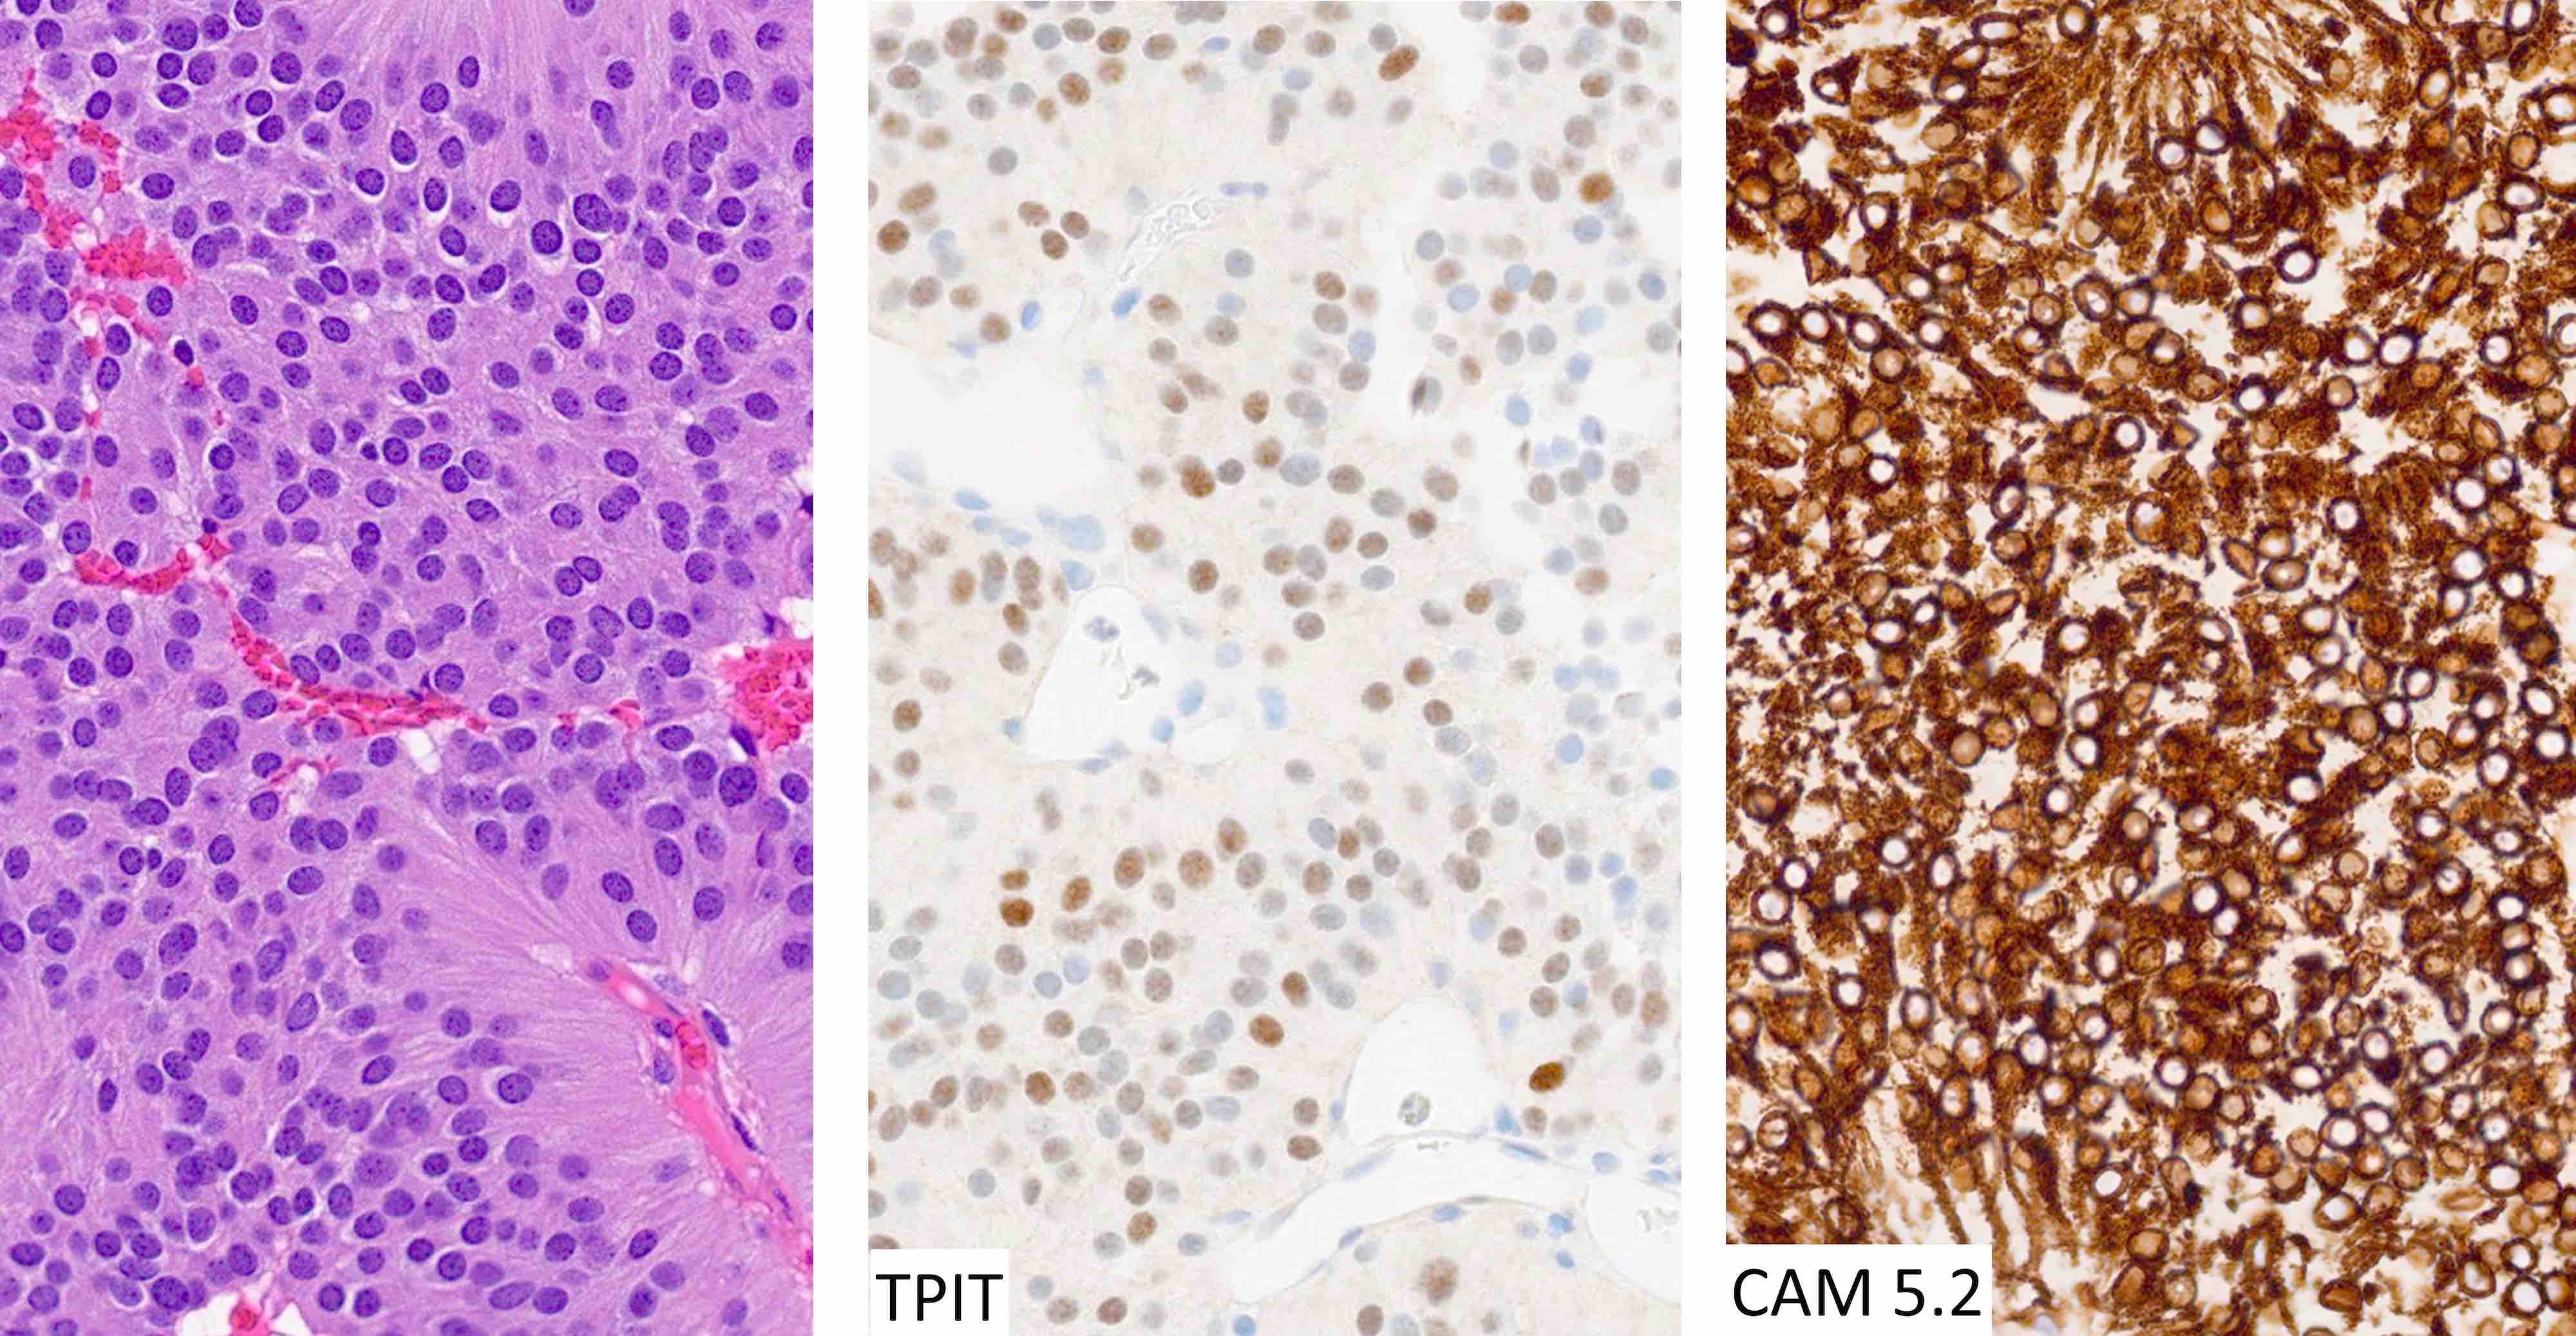

Microscopic (histologic) images

Contributed by Sylvia L. Asa, M.D., Ph.D.

Positive stains

- Stains for pituitary transcription factors (Pit1, Tpit, SF1, ER and GATA3) and hormones provide the basis for tumor classification (see Diagrams / tables)

- Diffuse and strong cytoplasmic CAM 5.2 staining is characteristic of corticotroph tumors

- Ring-like CAM 5.2 positivity is characteristic of Crooke cell tumors (Brain Pathol 2012;22:443)

The chromophobic tumor in the image above has the keratin pattern shown on the right. Which of the following is correct?

- This tumor stains for Tpit

Practice answer #2

A. This patient had acromegaly. This sparsely granulated somatotroph tumor stains for Pit1 (not Tpit) and causes acromegaly, which may be associated with hyperprolactinemia due to the stalk section effect since sparsely granulated tumors are often large at the time of diagnosis. These tumors generally do not respond to first generation somatostatin analogues. Somatotroph tumors do not cause Cushing disease.